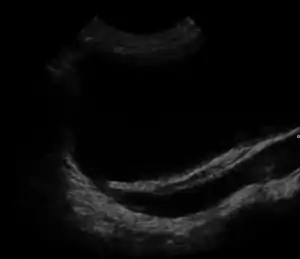

| Ultrasound image showing abnormal vesicoureteral junction and dilated distal ureter resulting in primary vesicoureteral reflux (VUR). | |